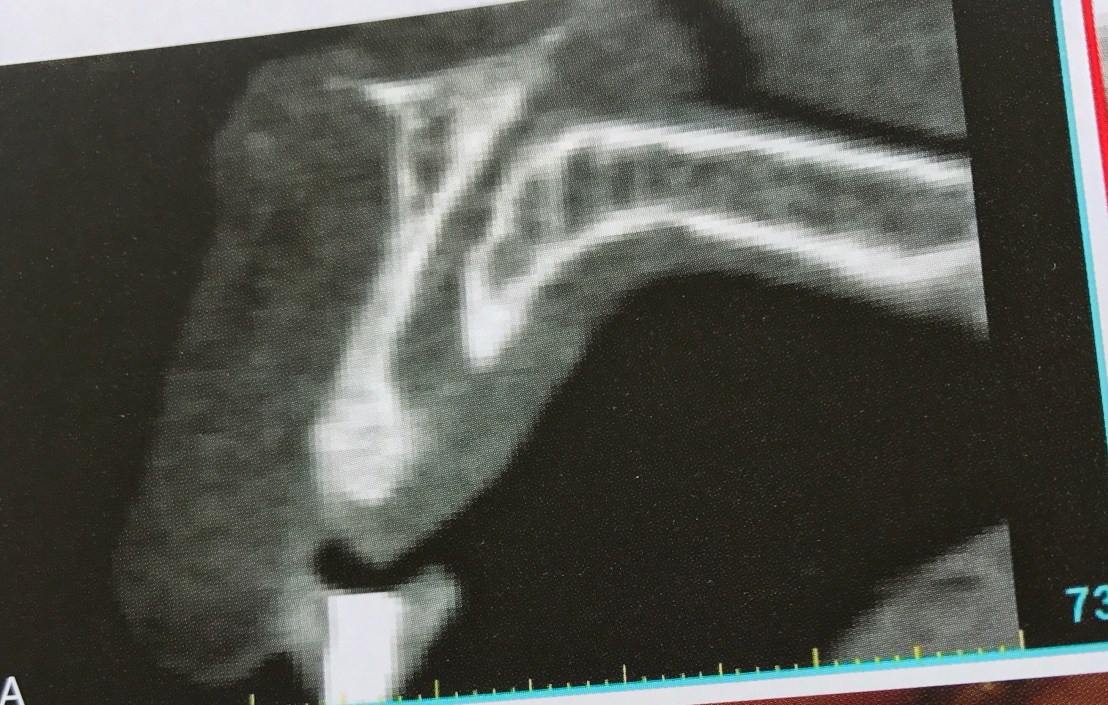

รูป A ด้าน Palatal คือ Nasopalatine canal ที่มีขนาดใหญ่มากในเคสนี้

รูป C คือ ความจำเป็นต้องฝัง Implant ในตำแหน่งนี้ครับ อันนี้คือ ฝังหลังจากย้าย Nerve ออกไปแล้วนะ

พบว่าตำแหน่งนี้ไม่ค่อยมีปัญหา อาจชาแบบ short term เพราะมักมี innervation จาก nerve อื่นเช่น Greater palatine nerve มาเลี้ยงภายหลัง

ให้ดูใกล้ๆ อีกครั้ง Nasopalatine canal ที่เชื่อม floor of nose กับ anterior palate